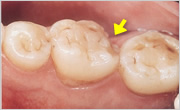

- CRACK

- クラック・ひび、亀裂

- CHIPPING

- チッピングやフラクチャー(破折)

- チッピング

- 奥歯の歯冠破折